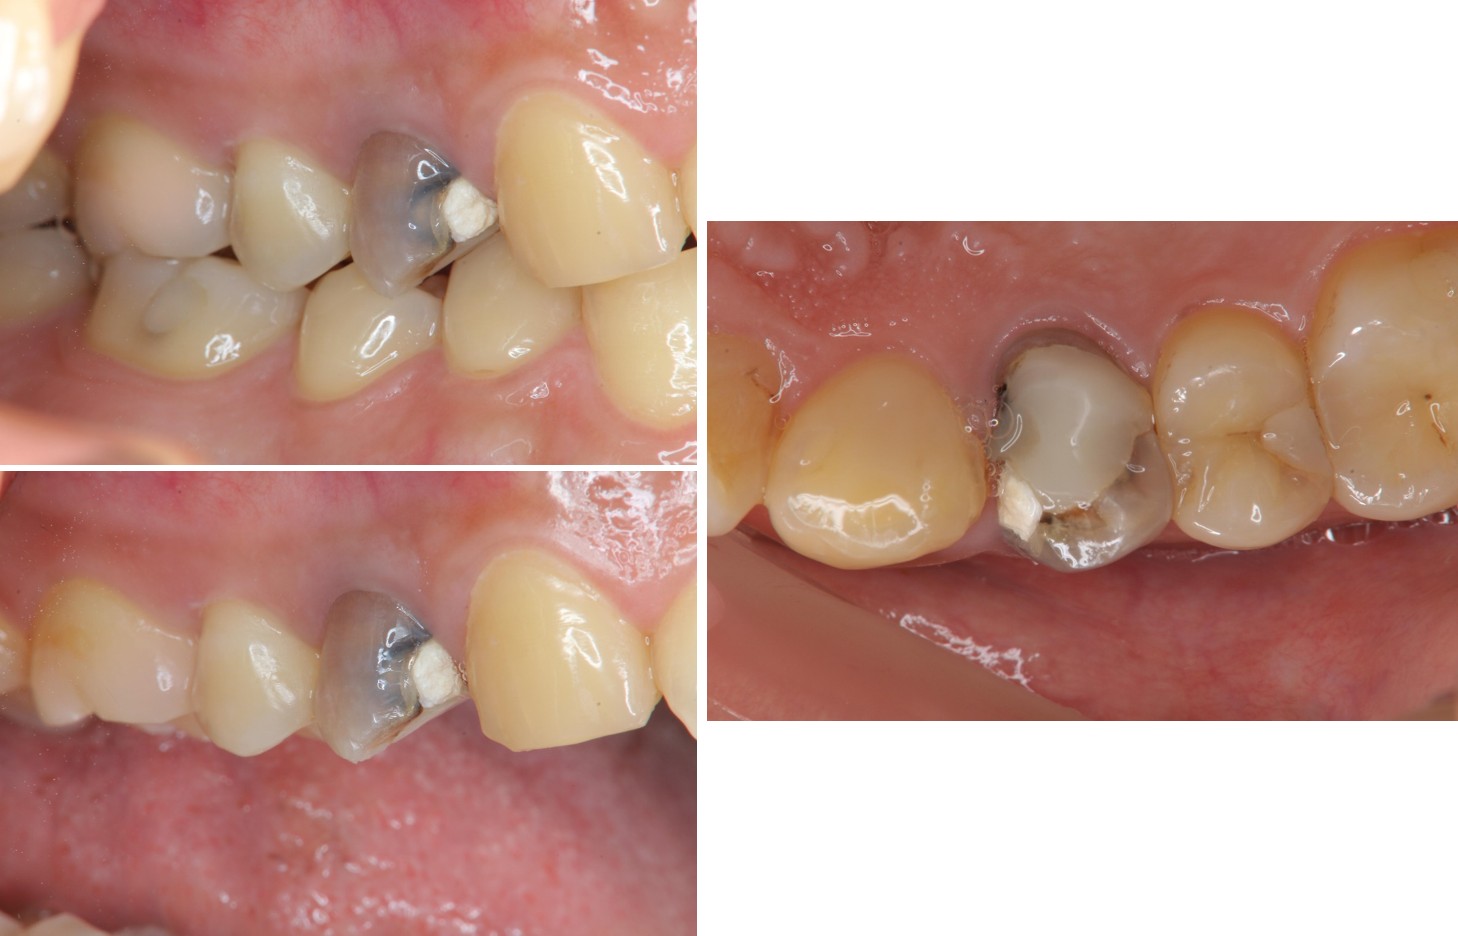

治療前,右上第一小臼齒疼痛

膺復前評估牙齦、牙齒狀態